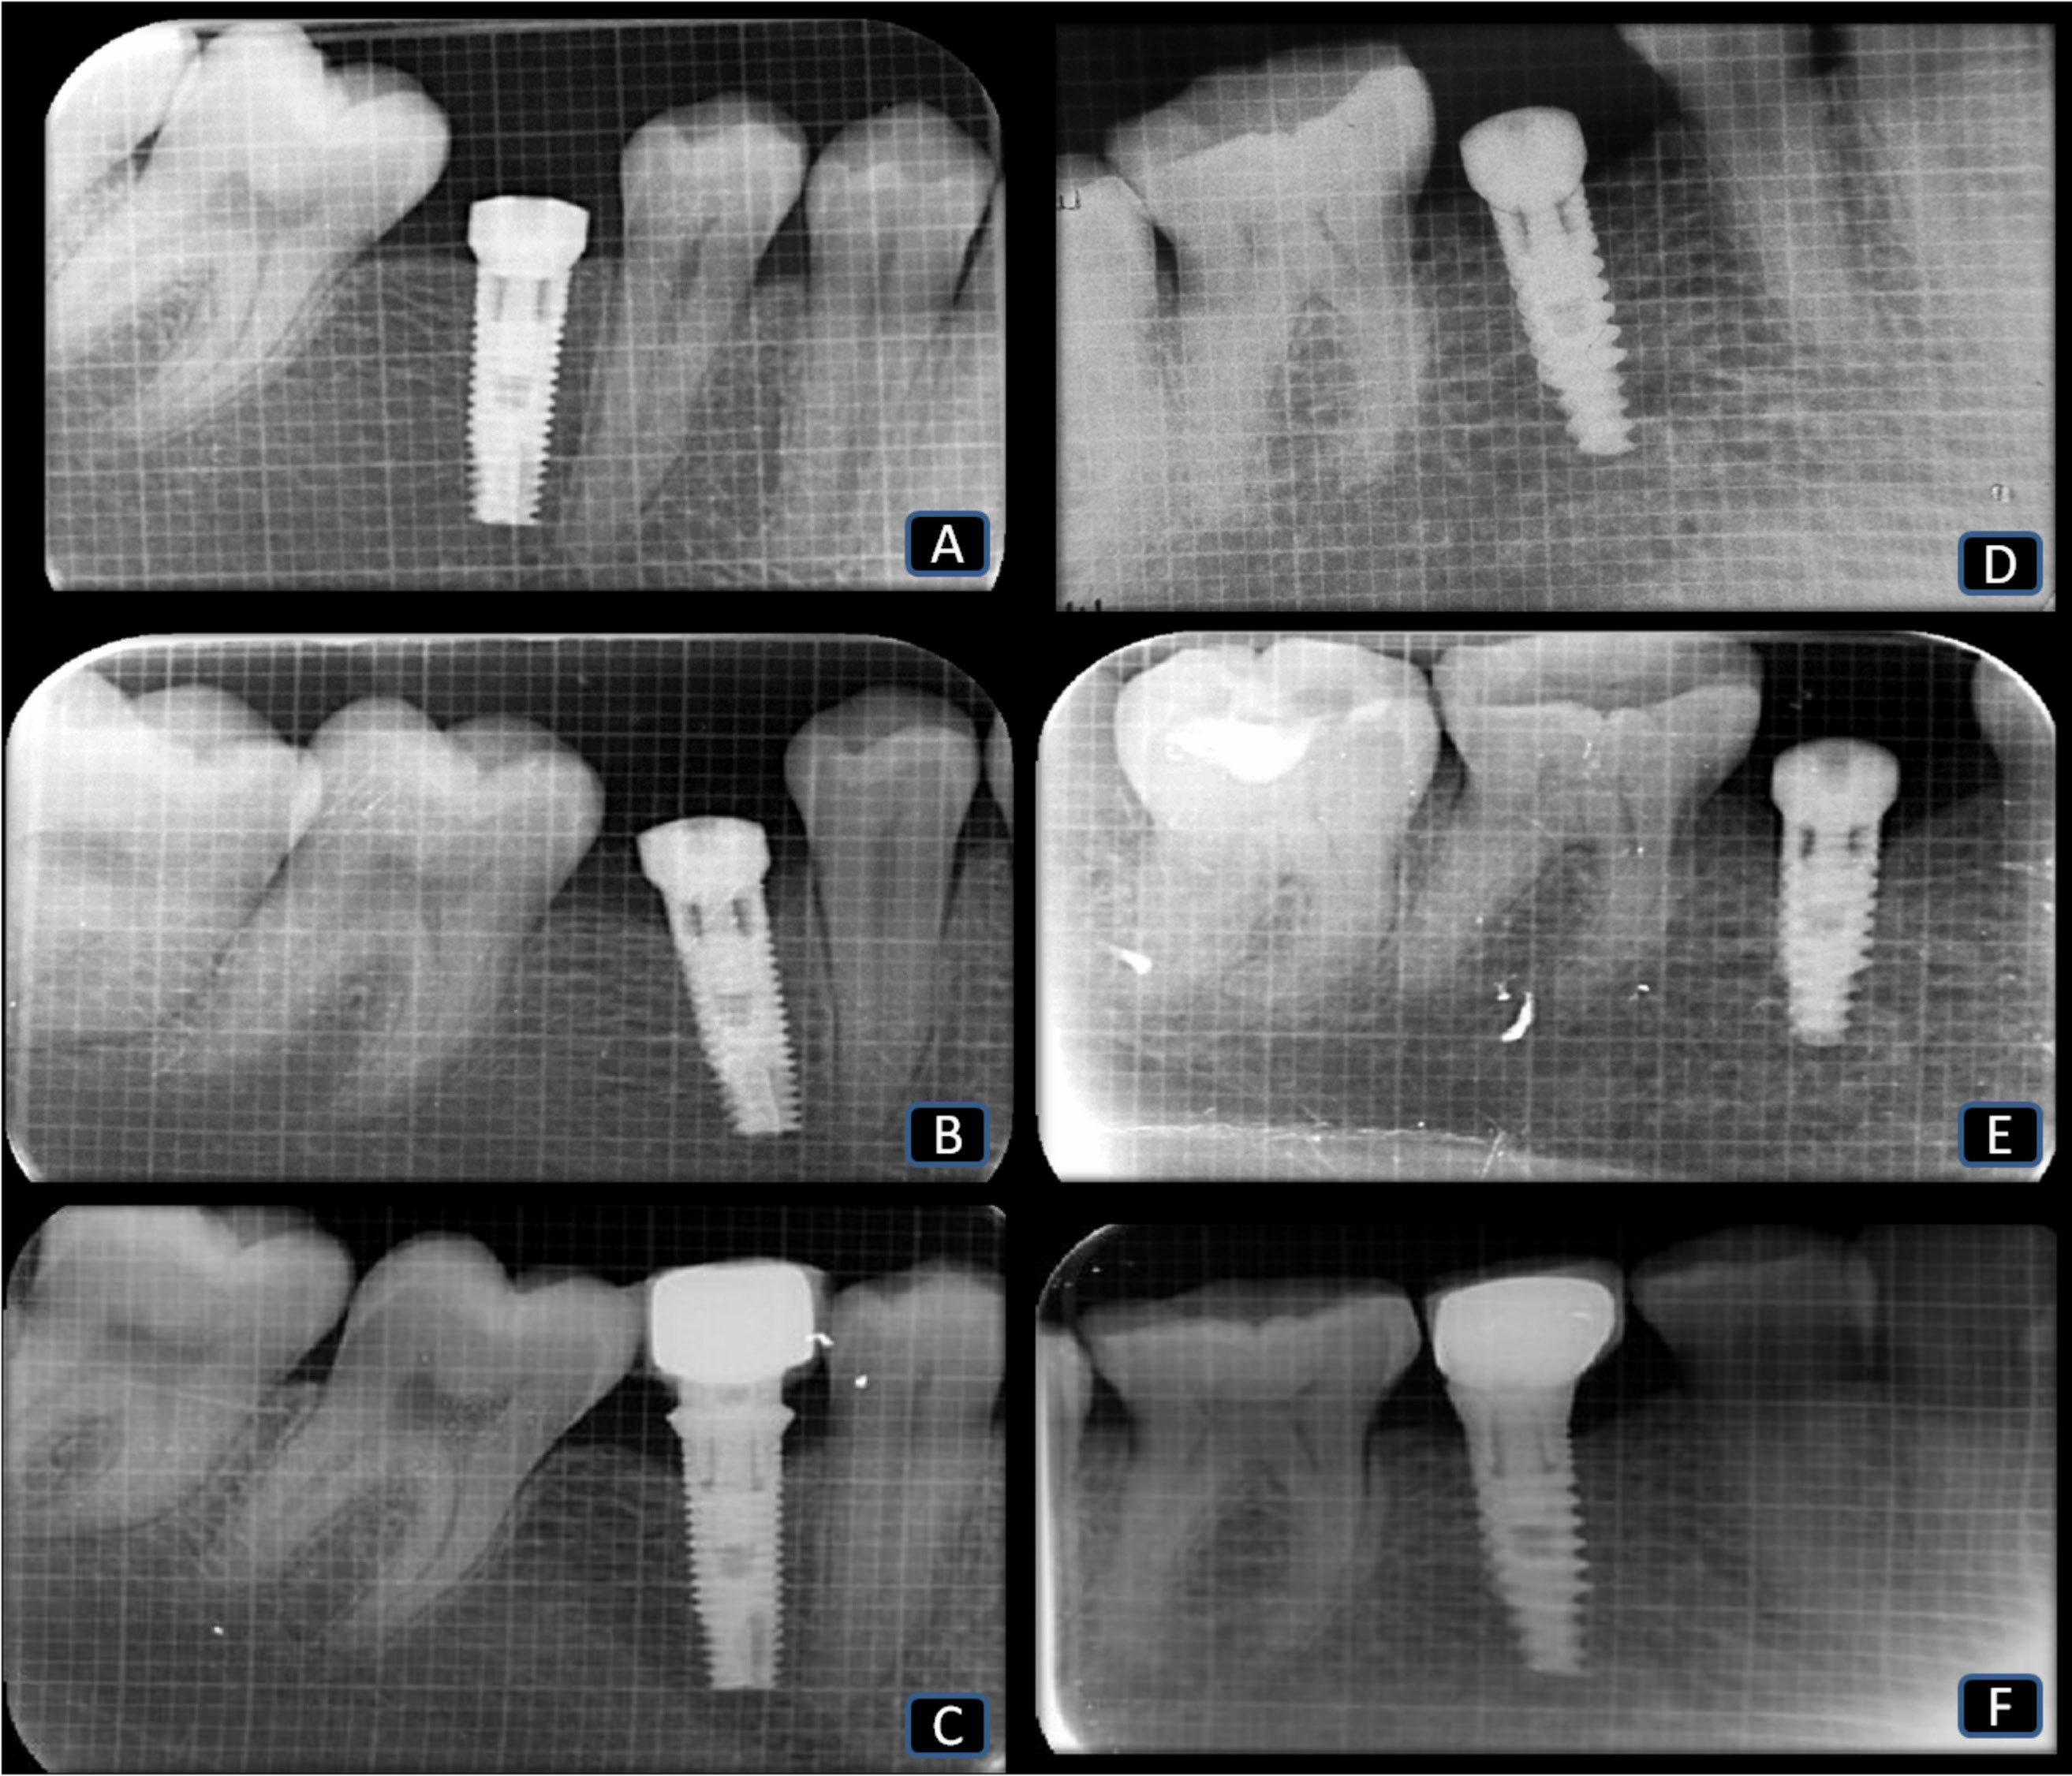

The outcome measures consisted of clinical parameters, including the modified plaque index (mPI),12 the gingival index (GI),13 the width of keratinized tissue (WKT),14 and the thickness of keratinized tissue (TKT).15 Radiographic parameters included CBL, measured using digital intraoral periapical radiography (IOPA).16 An independent examiner (R.D.), who was unaware of the study design, measured all clinical parameters. The WKT was measured using a calibrated manual periodontal probe between the gingival margin and the mucogingival junction (MGJ).14 The TKT was measured after anesthetizing the area using a 15-millimeter endodontic reamer by gently inserting it at the midpoint, 2 mm apical to the gingival margin on the facial aspect (perpendicular to the tooth surface), until the underlying hard structures were contacted, and the distance was measured with a University of North Carolina 15 (UNC 15) periodontal probe.15 Digital IOPA radiographs were taken using a 1 × 1 mm grid to measure CBL from the implant crest to the most apical point of the interproximal crestal bone on both the mesial (M) and distal (D) surfaces; an average value for these measurements was computed: (M + D)/2.16, 17

At 3 months post-op, the healing cap was replaced with a prosthetic abutment (Figure 2). The restoration was provided with a cement-retained porcelain-fused-to-metal ceramic crown (Figure 2). All outcome measures were evaluated immediately post-op (baseline), and at 3 months and 6 months post-op for both groups. Figure 3 shows the digital IOPA radiographs for both groups.

The CBL showed a statistically significant increase in both groups independently at 3 and 6 months post-op (p < 0.05), while the difference was not significant for the time interval 3 to 6 months. The mean difference in CBL from 3 to 6 months within group I was 0.43 ±0.53 mm, while it was 0.54 ±0.48 mm for group II. A statistically significant decrease in CBL was observed in group I vs. group II at the 3- and 6-month time points (p < 0.05) (Table 4, Table 5).